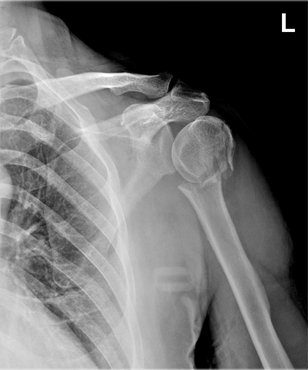

x-ray 사진

상완골 경부 골절, 수술 전